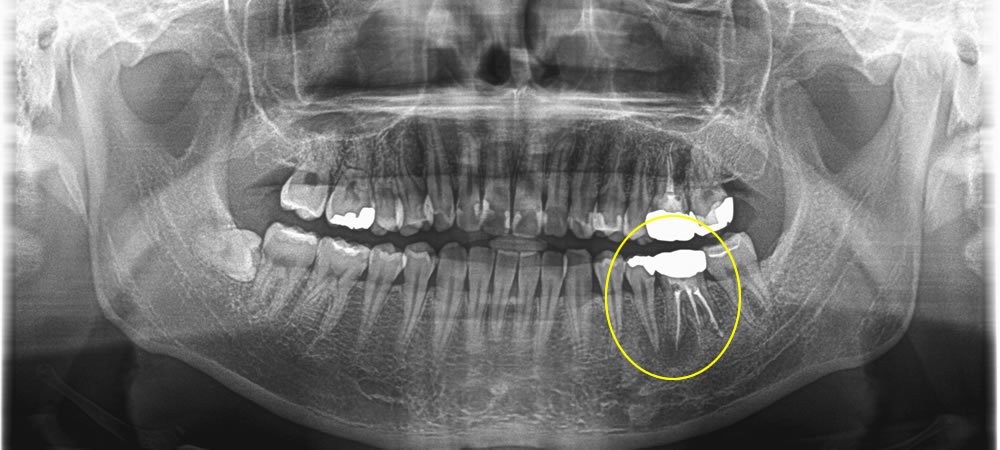

破折したインプラントを取り除いて再治療した症例

年齢

40代

性別

男性